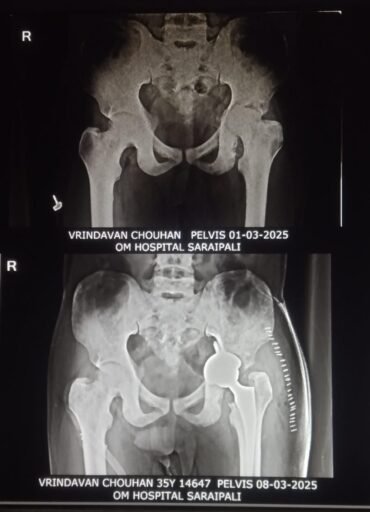

ओम हॉस्पिटल सरायपाली में 35 वर्षीय वृंदावन चौहान का सफल टोटल हिप रिप्लेसमेंट ऑपरेशन

सारायपाली: ओम हॉस्पिटल के डॉ. सौरभ अग्रवाल और उनके विशेषज्ञ टीम ने 35 वर्षीय वृंदावन चौहान का सफल टोटल हिप रिप्लेसमेंट ऑपरेशन किया। मरीज सिकल सेल डिजीज और हृदय संबंधी समस्याओं से पीड़ित थे, जिससे उनका ऑपरेशन काफी जटिल था, लेकिन डॉक्टरों की मेहनत और अनुभव से यह पूरी तरह सफल रहा।

डॉ. सौरभ अग्रवाल ने बताया कि सिकल सेल रोग के कारण मरीज के कूल्हे की हड्डी गंभीर रूप से प्रभावित हो चुकी थी, जिससे उसे असहनीय दर्द और चलने-फिरने में कठिनाई हो रही थी। इसके लिए मरीज ने आसपास के बहुत से अस्पताल में इलाज करवाया पर आराम नहीं मिला फिर वह ओम हॉस्पिटल सरायपाली में इलाज के लिए आया साथ ही, मरीज को हृदय संबंधित समस्या थी

जिसके कारण ऑपरेशन को विशेष सावधानी और विशेषज्ञ की देखरेख में किया गया।

सफल सर्जरी के बाद अब वृंदावन चौहान तेजी से स्वस्थ हो रहे हैं। मरीज को ऑपरेशन के दूसरे ही दिन चलाया गया। ओम हॉस्पिटल की टीम ने कहा कि वे आगे भी ऐसे जटिल और चुनौतीपूर्ण मामलों का इलाज कर मरीजों को बेहतर जीवन देने के लिए प्रतिबद्ध हैं। यह सफलता गंभीर कूल्हे की हड्डी रोग से जूझ रहे जटिल अन्य मरीजों के लिए एक नई उम्मीद है।